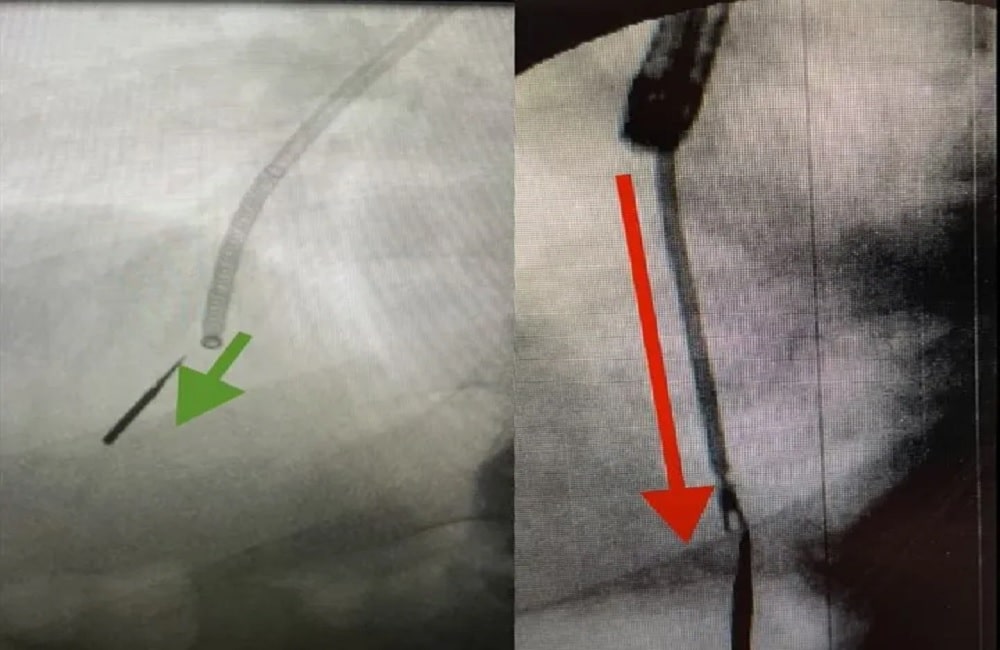

Μια συνηθισμένη επίσκεψη στον οδοντίατρο ήταν κάθε άλλο παρά φυσιολογική – για έναν άνδρα στο Ιλινόι των ΗΠΑ, ο οποίος «εισέπνευσε» την μύτη του οδοντιατρικού τροχού και χρειάστηκε να πάει στο νοσοκομείο για να την αφαιρέσει τον περασμένο μήνα.

Ο Τομ Τζόσι πήγε στο οδοντιατρείο για να κάνει σφράγισμα και τελικά έφυγε, έχοντας καταπιεί τμήμα του ιατρικού εργαλείου.

«Δεν το ένιωσα καν να κατεβαίνει. Το μόνο που ένιωσα ήταν ένας βήχας. Οταν έκαναν την αξονική τομογραφία κατάλαβαν και μου είπαν ″δεν το κατάπιες, το εισέπνευσες», περιγράφει ο ίδιος. Οι γιατροί πιστεύουν ότι το εισέπνευσε λίγο πριν βήξει, στέλνοντας το κομμάτι μήκους εκατοστών βαθιά στον πνεύμονά του.

Ο Δρ Aμντούλ Αλράιγες από το Ιατρικό Κέντρο Aurora-Kenosha στο Ουισκόνσιν, είπε ότι το κομμάτι ήταν τόσο βαθιά που με τα εργαλεία του δεν μπορούσε να το φτάσει. Ωστόσο, ο άτυχος άνδρας ενημερώθηκε ότι εάν οι γιατροί δεν κατάφερναν να αφαιρέσουν τη μύτη του τροχού, θα έπρεπε να του αφαιρέσουν μέρος του πνεύμονά του.

Η ιατρική του ομάδα αποφάσισε να δοκιμάσει μια προηγμένη συσκευή, που έχει σχεδιαστεί για την έγκαιρη ανίχνευση του καρκίνου.

Ετσι κατάφερε να εισχωρήσει στους στενούς αεραγωγούς, να φτάσει το αντικείμενο και να το τραβήξει έξω χωρίς να βλάψει τον Τζόσι.